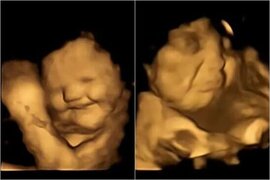

Kök və brokkoli yeyən hamilələrin bətnindəki körpələrin reaksiyaları güldürdü - FOTO

Salat bəzi insanlar üçün əvəzsiz qida sayılsa da, digərləri üçün bir qab tərəvəz yemək fikri daha çox cəza kimi səslənir. Tədqiqatlar isə göstərib ki, bu təkcə uşaqlara, yaxud yetkinlərə aid məsələ deyil, hətta hətta ana bətnin olan körpələrin də fərqli dad zövqləri olur. Bu barədə Durham Universitetini